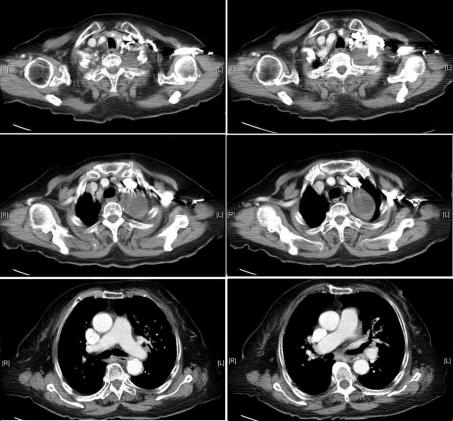

Syncope is a common complaint in clinical medical care. The etiology and mechanism can be complex. We report two cases experienced recurrent syncope to our emergency room without concomitant symptom. The image studies of both cases revealed apical neoplasms compress left common carotid artery with mediastinal lymphadenopathy and without cardiac/main artery trunk involved. After brain lesion, cardiac arrhythmia, and orthostatic hypotension were excluded, syncope related to vagus nerve involved was suspected.

https://cdn.ncbi.nlm.nih.gov/pmc/blobs/984d/3279508/114c6a962700/jocmr-04-77-g001.jpg